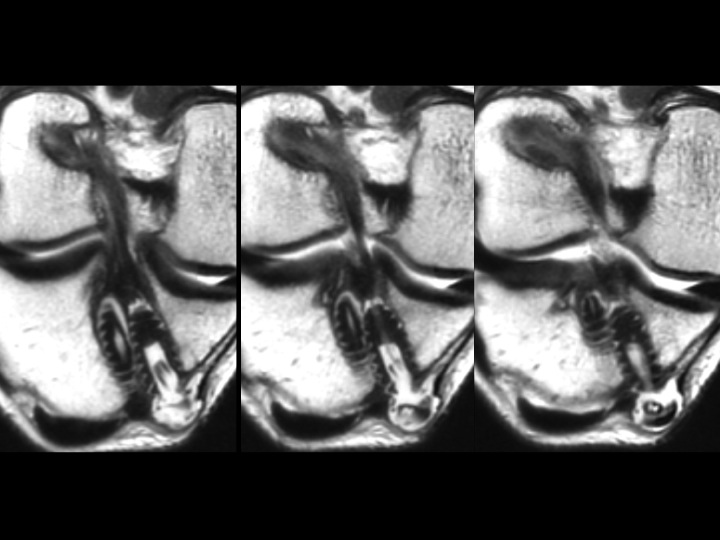

Figure 1 for case ACL graft device ( RID5523 )

Figure 1

There is fragmentation of one of the 2 bioabsorbable interference screws in the tibial tunnel, with a fragment situation in a cyst superficial to the tibial tunnel. The ACL graft is markedly attenuated. The last slide shows the failed, fragmented bioabsorbable femoral crosspin (arrow) from the initial reconstruction in 2011. Might be time for a Bone-Patellar Tendon-Bone autograft with metallic fixation?